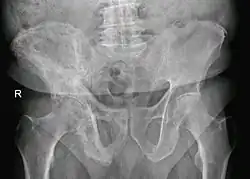

Maladie de Paget, os coxal droit. Homme de 80 ans.

En règle générale, la radiographie et l'élévation des phosphatases alcalines suffisent pour porter le diagnostic de maladie de Paget.

L'aspect radiologique est typique avec une déformation des os comprenant des zones déminéralisées et des zones de condensation.